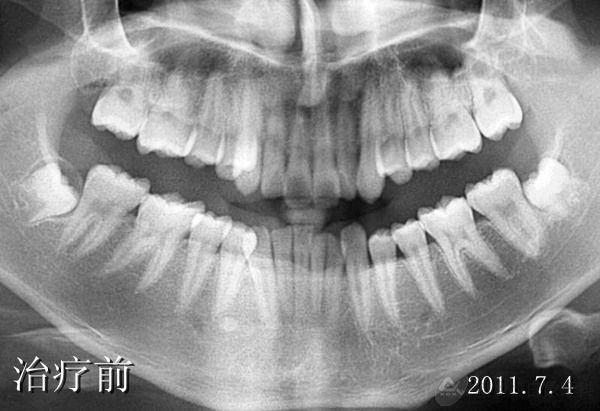

发布时间: 2014-06-27      患者李某某, 男,因“牙不齐、影响美观”来院治疗。初诊时间2011年7月4日,结束时间2014年5月1日。 接诊医生:李呈遥 患者非常满意,现将病例做一回顾性展示:

患者李某某, 男,因“牙不齐、影响美观”来院治疗。初诊时间2011年7月4日,结束时间2014年5月1日。

接诊医生:李呈遥

患者非常满意,现将病例做一回顾性展示: